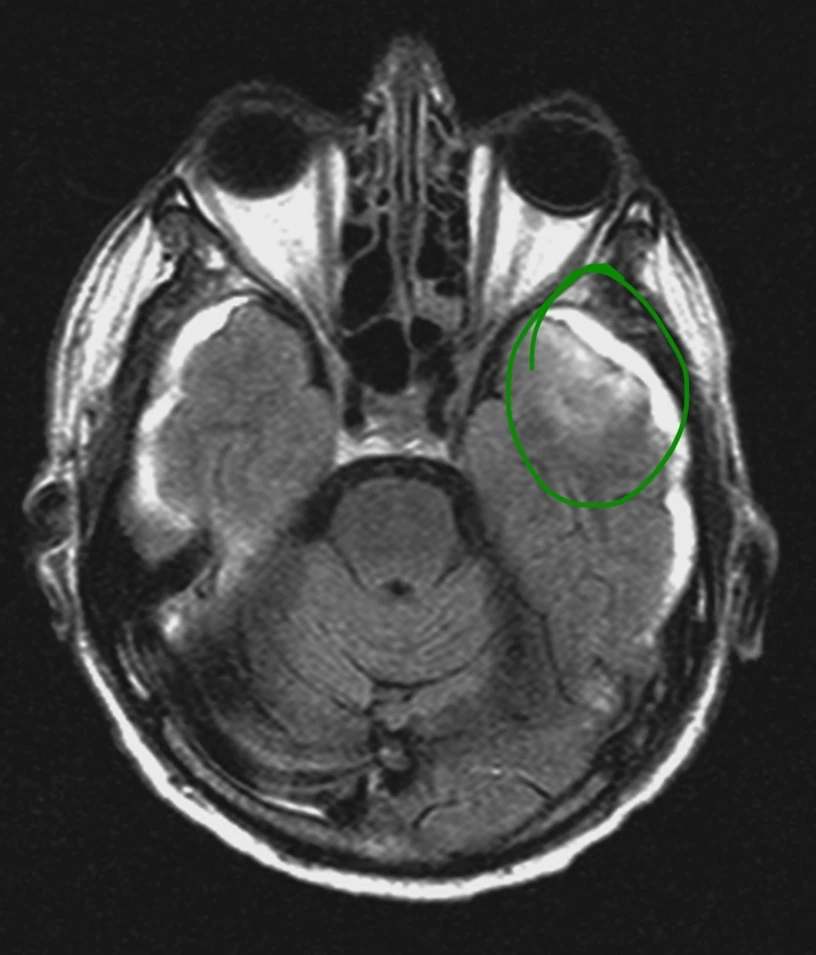

Женщина 32 года. Больной считает себя с 2024 г, когда стала отмечать онемение угла рта. Со слов пациентки ей был предварительно выставлен диагноз - РС, но дополнительных методов обследования и специфического лечения не проводилось. В настоящее время жалоб нет. В исследовании от октября 2024 отмечался очаг в левой затылочной доле с выраженным контрастированием, в настоящее время этот же очаг отмечается с сохраняющимся контрастированием. Формально - есть выполнение критериев диссеминации и в пространстве (юкстакортикальный и перивентрикулярный очаги есть), и во времени (есть усиливающиеся и неусиливающиеся очаги), клиника тоже вполне укладывается. Но! Найти в литературе подобных случаев мне не удалось, видел сам и максимум, что находил в литературе - полгода контрастирования. Получается, мы имеем дело с крайне атипичным рассеянным склерозом, или это не рассеянный склероз. А тогда что? Сосудистая мальформация не вариант - на SWI не видать. Какая-то ганглиоглиома? А другие очаги тогда что? Есть соображения? Кстати, диффузия стойко повышенная, и на б1000 почти не видно (изо). На Т2 не меняется